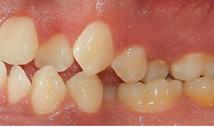

Estudios de inicio intraorales

Fotografías en la lateral derecha tenemos: relación molar clase I bilateral y relación canina clase I bilateral, líneas medias dentales coincidentes (Figura 3), -5 mm de overjet, 10% de underbite, las arcadas superior e inferior son ovaladas, apiñamiento severo superior e inferior (Figura 4).

Estudios de inicio intraorales en la fotografía de frente, tenemos la línea media dental superior se encuentra desviada a 1 mm a la izquierda y la línea media dental inferior se encuentra desviada 2 mm a la derecha (Figura 2). En la oclusal superior la forma de arco cuadrada (Figura 3). En la lateral derecha una relación molar clase II y relación canina clase II (Figura 4), izquierda una relación

molar clase II y relación canina clase II.